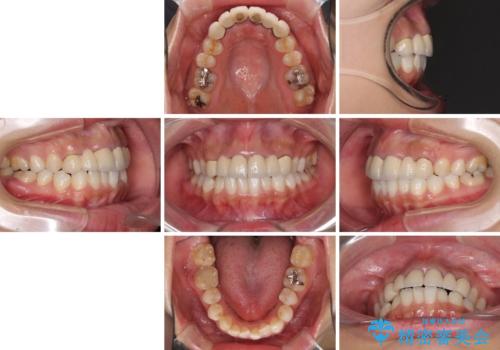

- 審美的ではない上の前歯とデコボコの下の前歯、歯茎が腫れている奥歯を気にして来院された患者様です。

根管治療の必要な歯がいくつかあるため、まずは根管治療を行い、その後インビザラインにて矯正治療を行うこととしました。

矯正治療後に前歯をセラミックブリッジに、奥の銀歯はセラミックインレーやPGAインレー(ゴールドインレー)にて補綴・修復治療を行うこととしました。